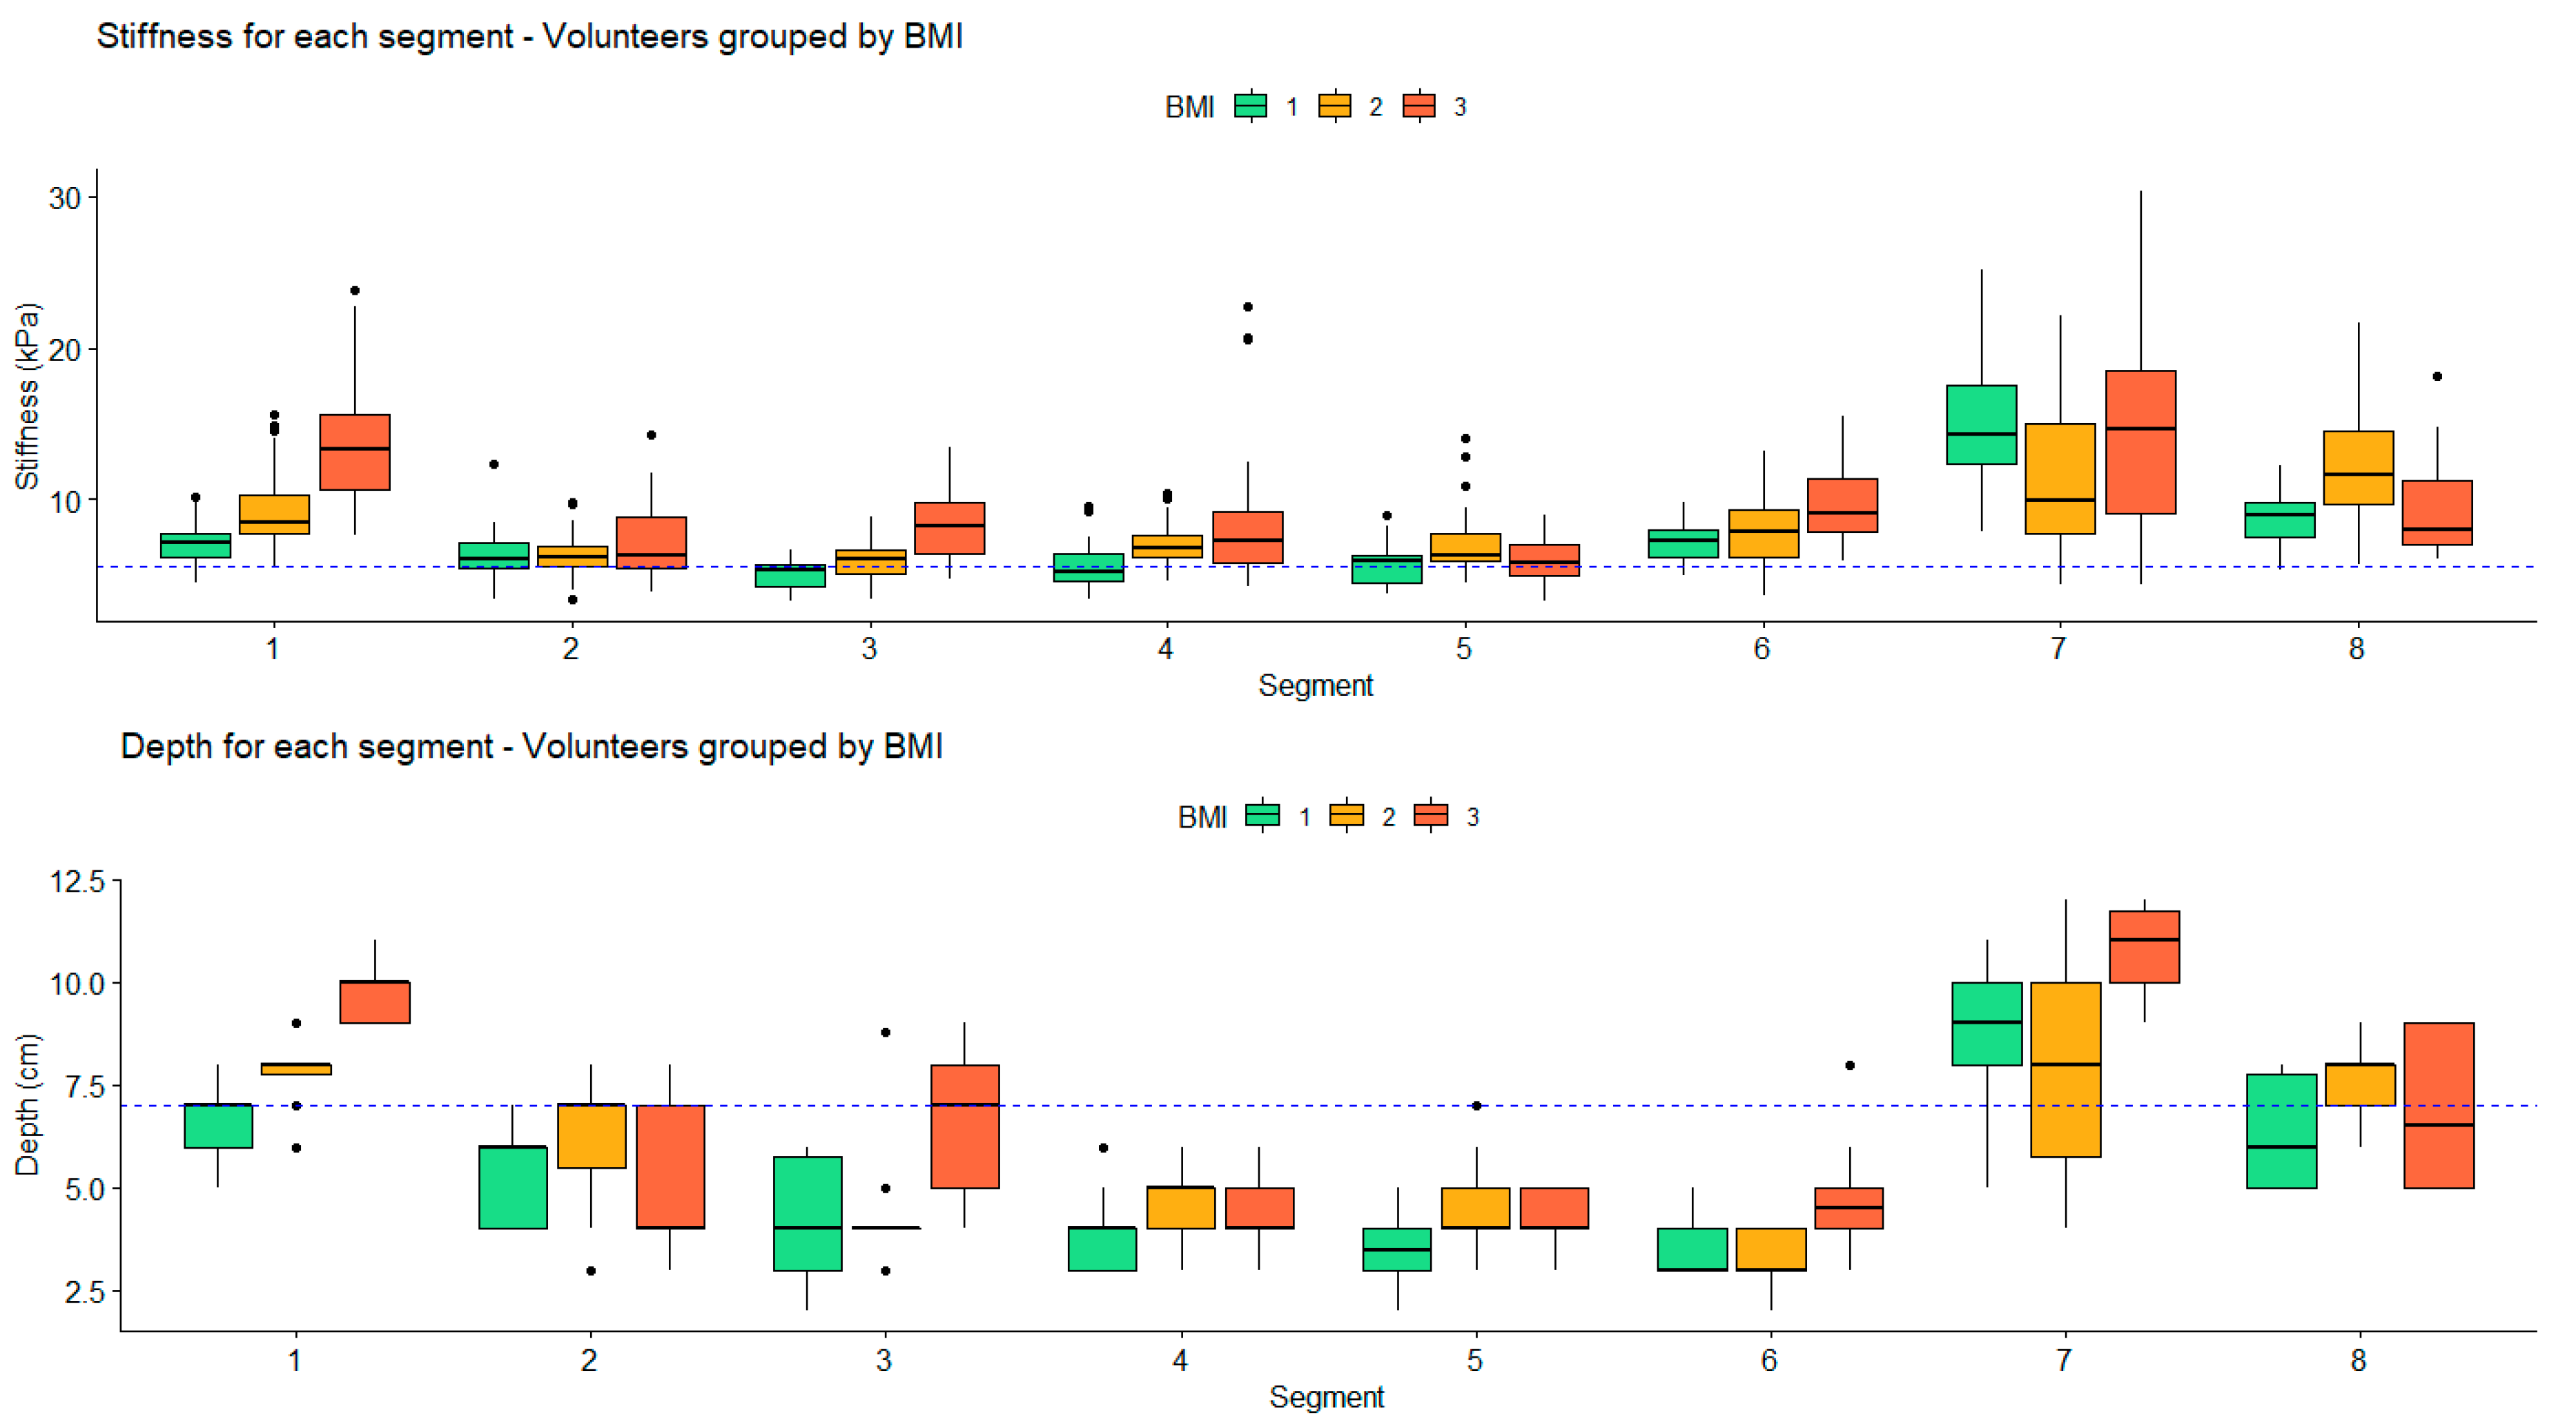

Impact of Depth and Acquisition Protocol on Hepatic Segment Stiffness Measurements

3.3. Robustness of Texture Features in Healthy Livers